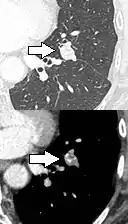

Round well-delineated solid lung nodule with smooth border.[9]